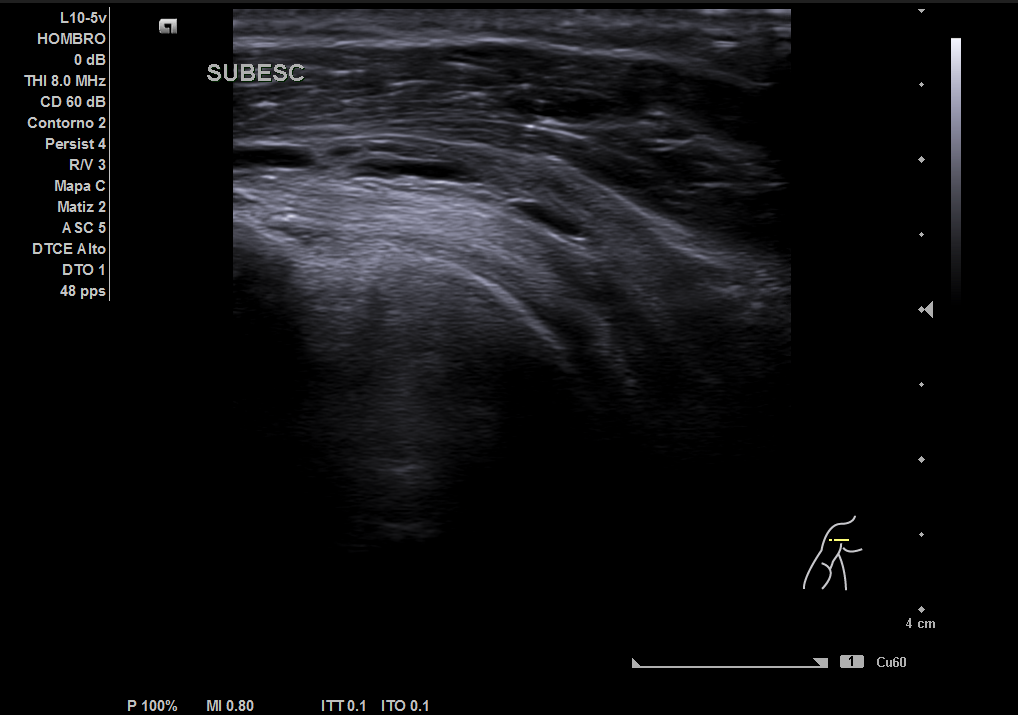

En la ecografía realizada observamos una rotura completa del tendón supraespino, rotura parcial del subescapular y severo derrame peritendón del bíceps junto con derrame articular glenohumeral.

Juicio diagnóstico: rotura manguito de los rotadores (rotura completa supraespinoso).